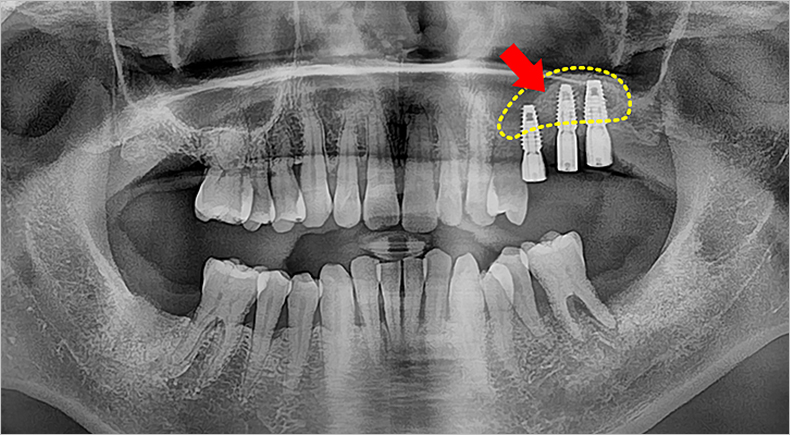

상악동거상술이란?

상악동은 얼굴의 코와 광대뼈 사이 안쪽에 있는 빈공간을 말하는데요, 상악동은 뼈가 없는 공간이기 때문에 임플란트를 식립하기가 어렵기도 하지만 사람에 따라서는 상악동이 치아 부분까지 내려오는 경우가 있습니다. 이 때 상악동을 위로 밀어올려 그 부위에 뼈이식을 함으로써 임플란트를 시술할 수 있는 충분한 공간을 확보하는 시술을 '상악동거상술'이라고 합니다.